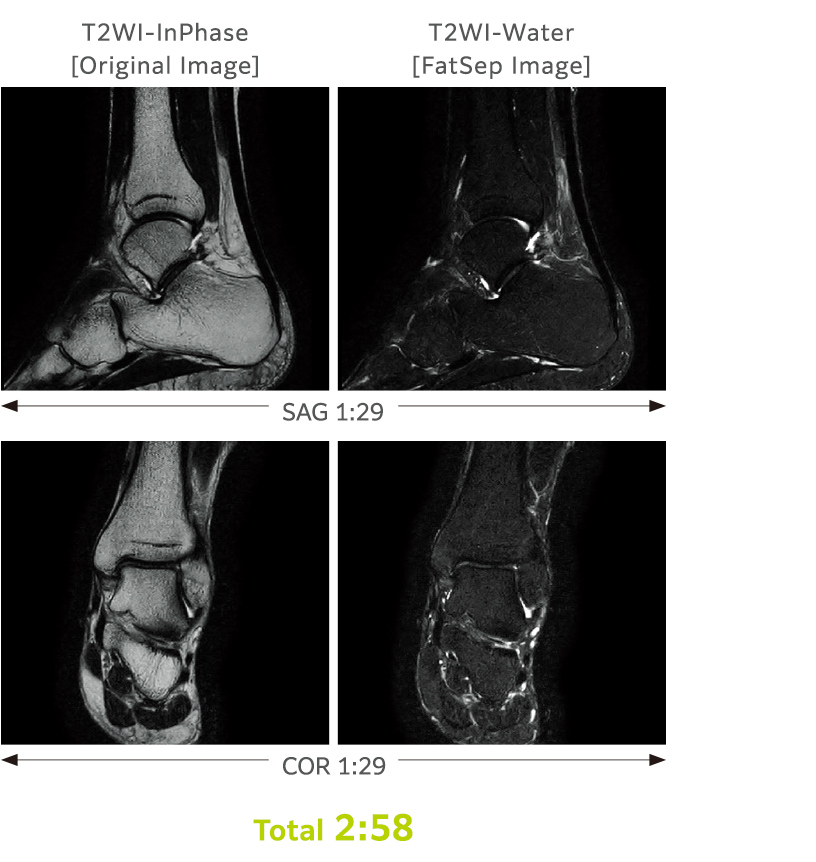

FatSep ist eine Art von Unterdrückungsmethode und wird weniger durch Änderungen der magnetischen Empfindlichkeit beeinflusst.

Mit einem einzigen Scan können mehrere Bilder unter Ausnutzung der unterschiedlichen Resonanzfrequenzen (chemische Verschiebungen von Wasserprotonen und Fettprotonen) gewonnen werden.